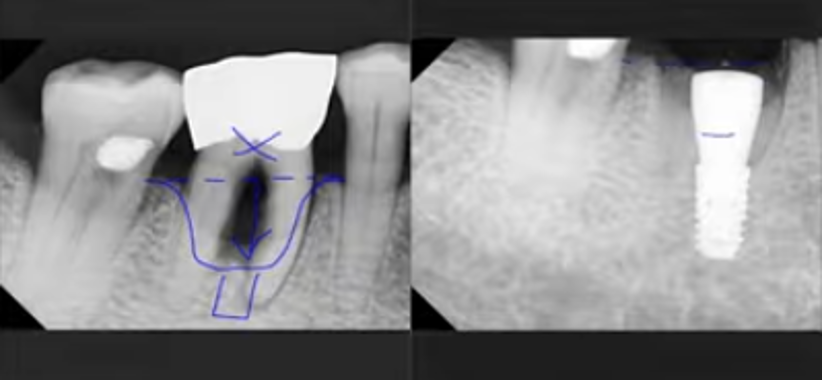

CASE.7 타 치과에서 깨진 임플란트 재수술..